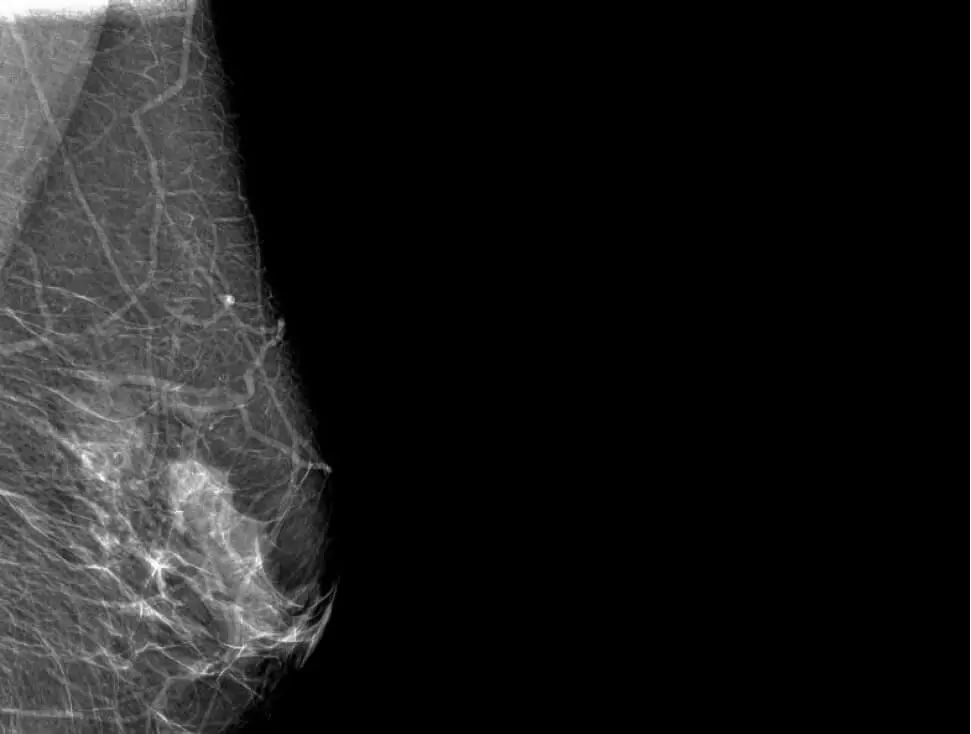

L CC R CC

L MLOR MLO

An AI-powered solution efficiently detects pathologies in medical imaging, including cancer, cancer nodules in the early stages. It supports X-rays, CT scans, and MRIs, reducing diagnosis time and enhancing hospital capacity by streamlining workflows.